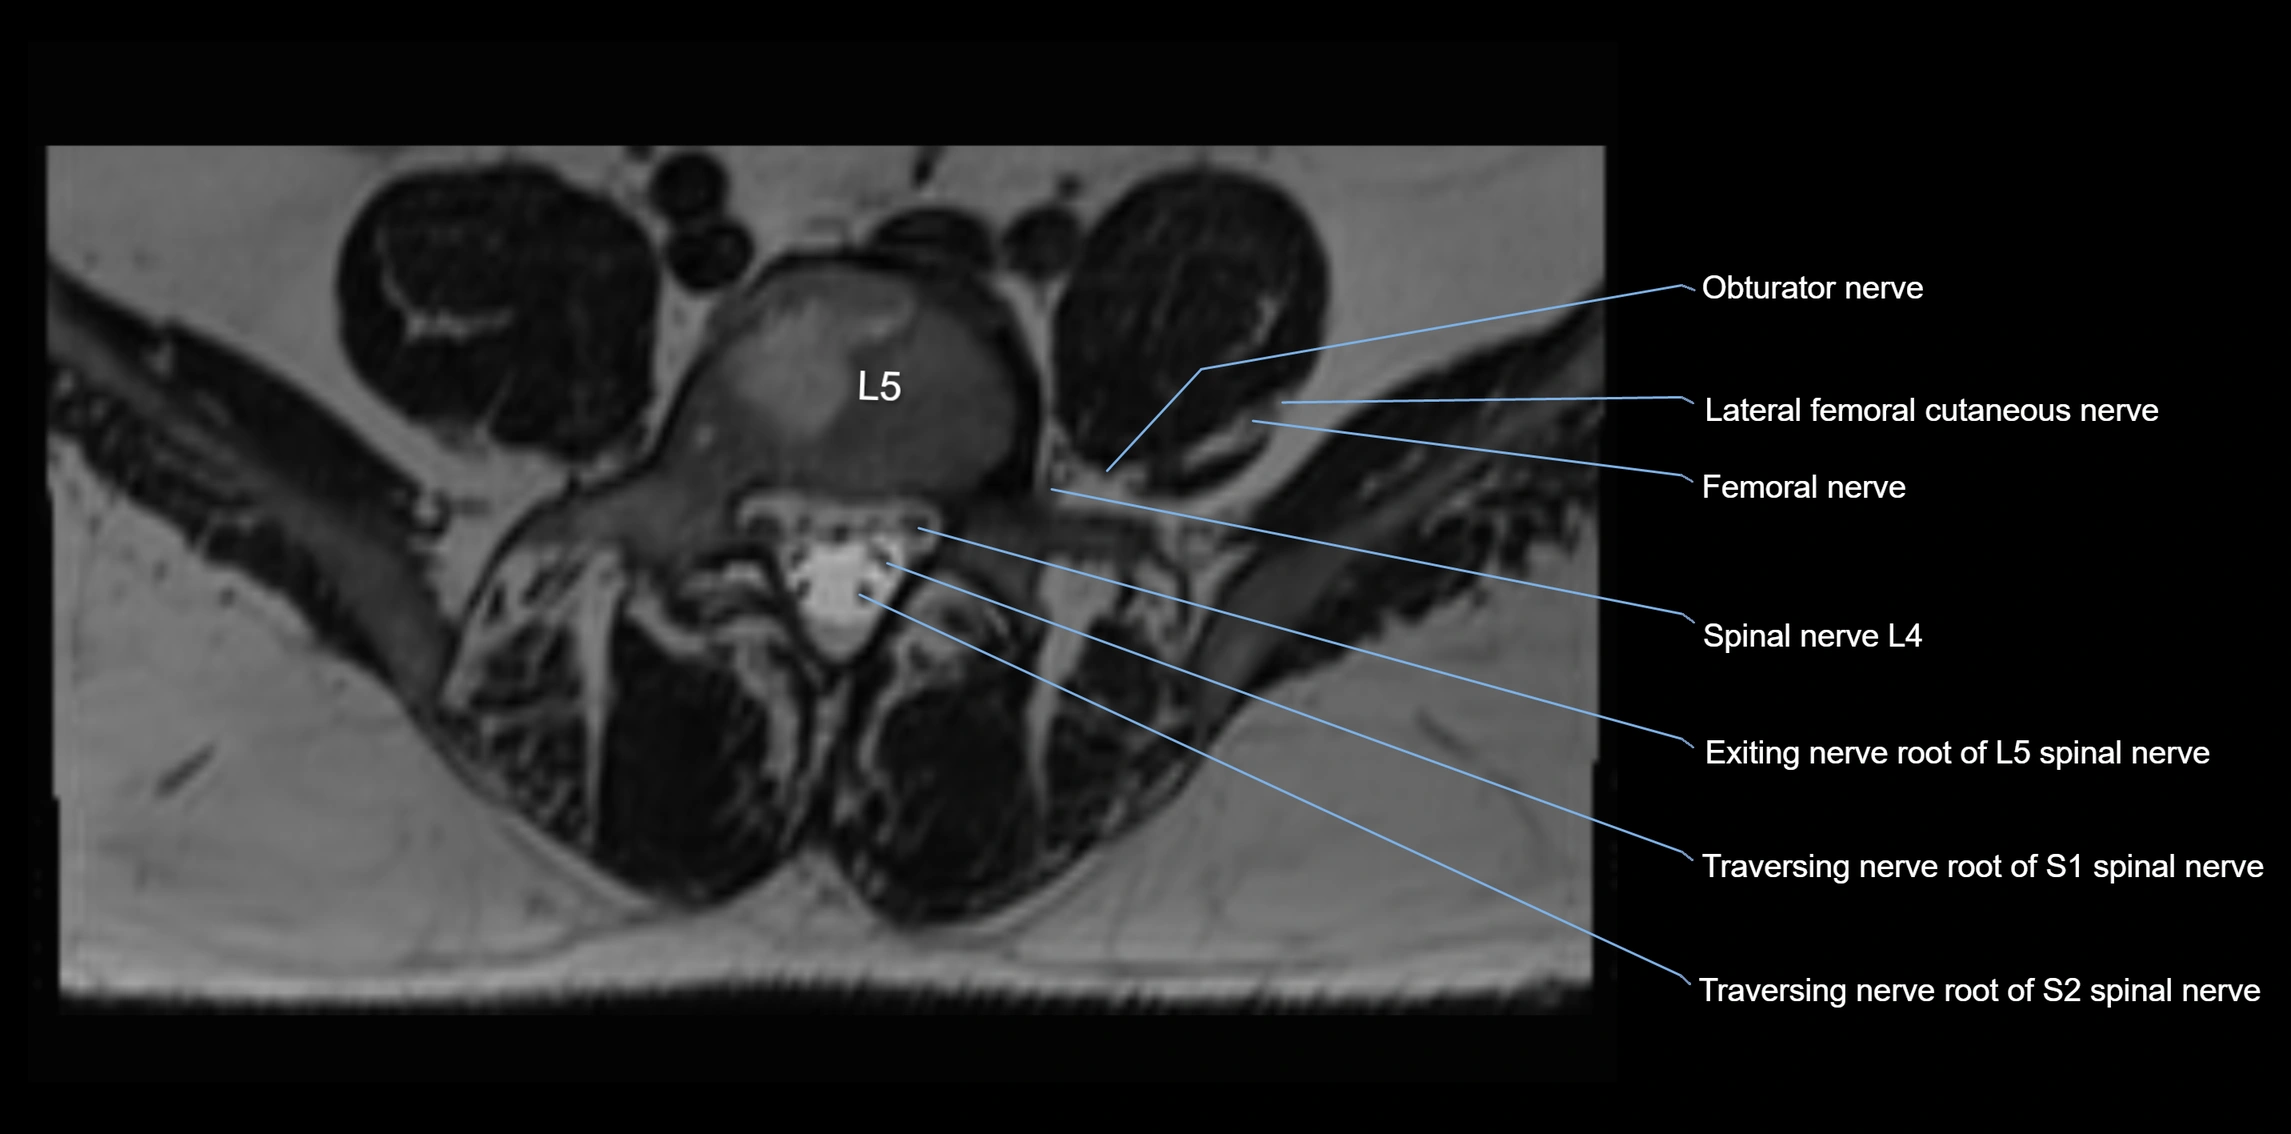

MRI image

image